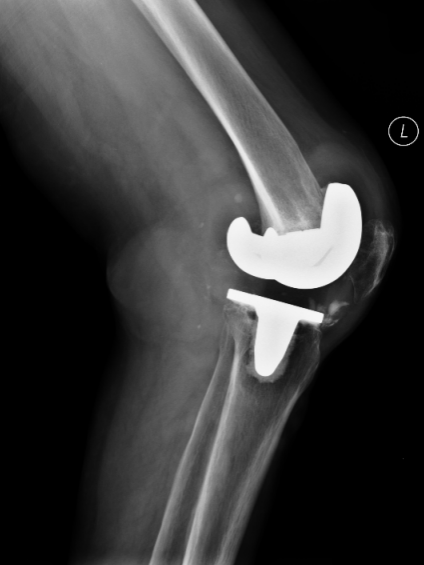

经详细查体,发现陈女士左膝关节肿胀明显、内翻畸形,关节脱位,无法行走,X线片显示,假体松动,内侧股骨髁、内侧胫骨平台部分骨溶解,左下肢内翻畸形,确诊为“左侧人工膝关节置换术后假体松动”并收住晋江市医院骨科。

▲ X线提示:假体松动,内侧股骨髁、

内侧胫骨平台部分骨溶解,左下肢内翻畸形

▲ 术后X线提示:关节位置良好,关节关系正常